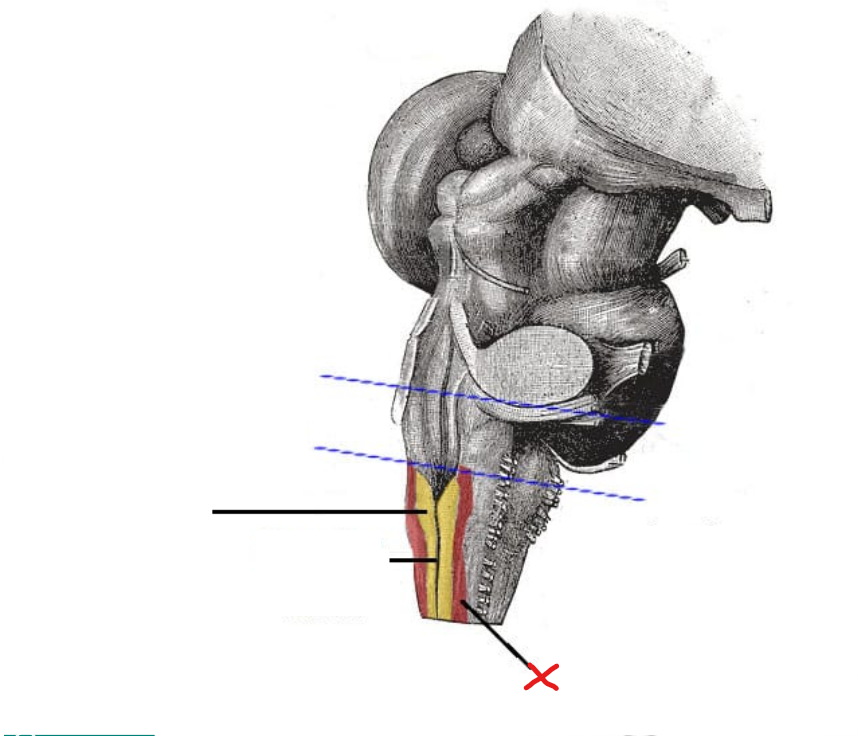

3

Dorsal median sulcus

What is X

Fasciculus gracilis

Fasciculus cuneatus

What are the fasciculus gracilis and fasciculus cuneatus together called

Dorsal column

Are the dorsal columns ascending or descending tracts

Ascending tracts

Where do the ascending tracts begin in

Spinal cord

Where do the ascending tracts terminate in

Medulla in nucleus gracilis and nucleus cuneatus

5

Gracile tubercle

1

Cuneate tubercle

Posterior median sulcus